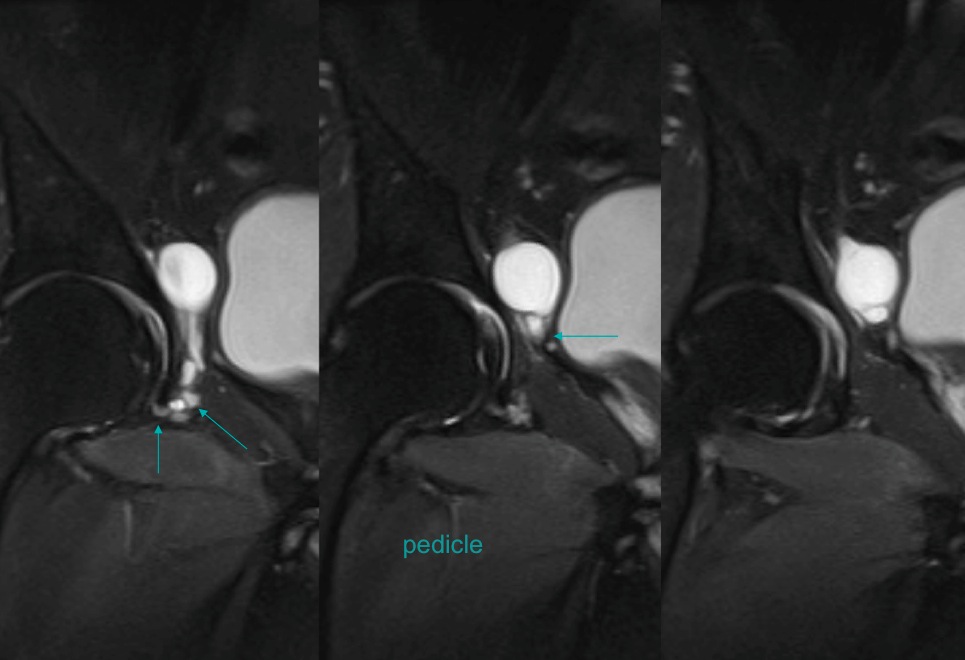

Figure 5 for case Obturator nerve impinge by ganglion cyst

Figure 5

Figure 6 for case Obturator nerve impinge by ganglion cyst

Figure 6